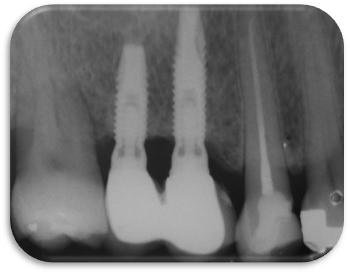

Imagem do artigo

Figura 5. Radiografia periapical dos implantes instalados na região do 16 e 17 após 8 anos em função. Importante observar que a perda óssea peri-implantar limita-se à porção usinada dos implantes e que esta perda é provavelmente devido à readaptação das distâncias biológicas.